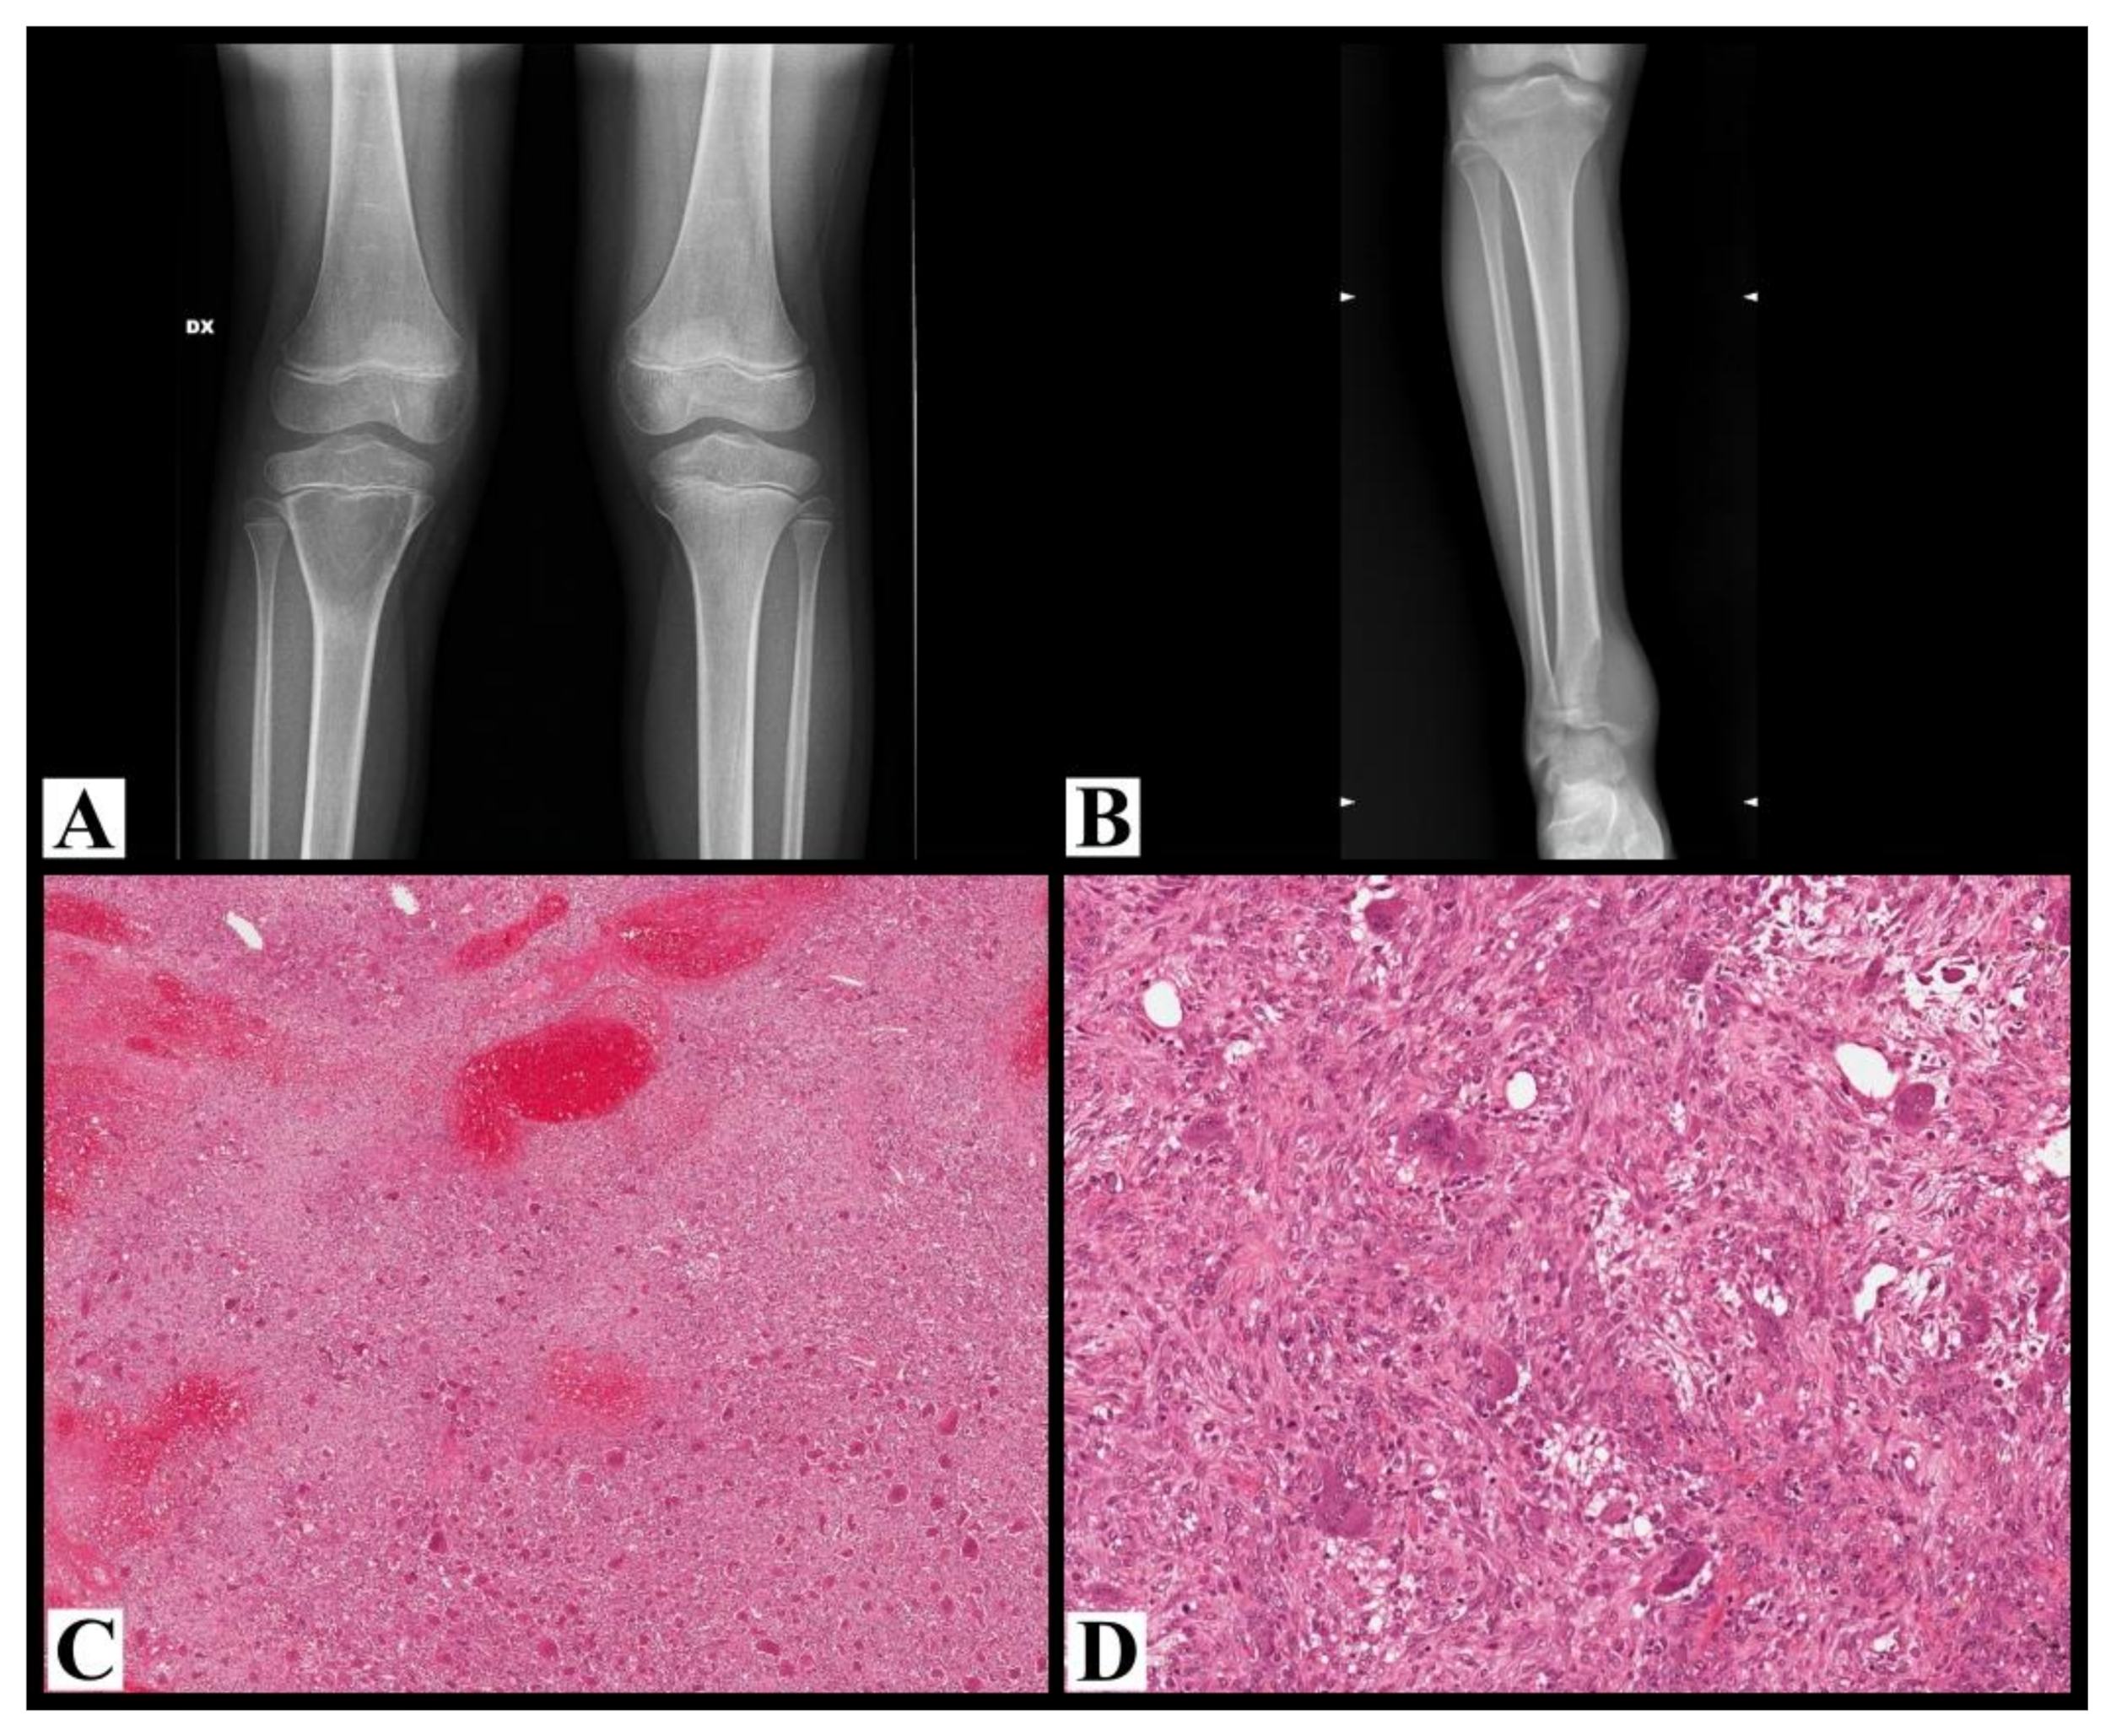

Fourteen patients were female and only one was male. The mean and median age was 13 years old (range 8–15). In 5 cases (7, 8, 10, 11, and 14) initial imaging was not available and the location was only described in the radiological reports. In cases with available imaging, in long bones, two cases (cases 1 and 2) occurring in skeletally immature patients with an open growth plate were purely metaphyseal and centrally located (Figure 2A), while the seven cases occurring in skeletally mature patients with a closed growth plate were meta-epiphyseal and eccentric (case 15, Figure 2B).

Histologically, all cases showed typical histological features of GCTB (Figure 2C,D).

In adult patients, the typical location of GCTB is in the meta-epiphyseal region of long bones, eccentrically. In our series, considering the cases occurring in long bones with available imaging (nine cases), in the two skeletally immature patients with an open growth plate (case 1 and 2), the lesions were purely metaphyseal and centrally located, while in the seven patients with a closed growth plate, the lesions were meta-epiphyseal and eccentric. This does not exactly correspond to the description of Campanacci [10] of a prevalent pure metaphyseal location in pediatric patients. However, if we consider the skeletal age of the patient and the status of the growth plate, the fact that the lesions showed a pure metaphyseal location in the two skeletally immature patients supports the hypothesis of a metaphyseal origin of GCTB. In the literature, it is difficult to check the exact correspondence between the status of the growth plate and the location of the lesions, since this is not described in each series. Picci et al. [9] described six cases of GCTB in skeletally immature patients with an open growth plate; with the limitation that these cases were not tested for the presence of H3F3A mutation, all of them showed a predominant metaphyseal location, with extension into the epiphysis in five patients, thus demonstrating that the presence of an open growth plate does not preclude the possibility of an epiphyseal extension, beyond the physis.

Figure 2. (A) Plane X-ray of the knee shows a purely lytic, centrally located lesion in the proximal metaphysis of the tibia with relatively well-defined margins underneath an immature growth plate; the cortex is thinned without interruptions (case 1). (B) Plane X-ray of the ankle shows osteolysis of the distal tibia located in the meta-epiphyseal region with aggressive radiological features: not well-defined margins, cortex expanded and interrupted, growth plate invaded and crossed (case 15). (C) Histological examples of giant cell tumor of the bone (case 14), with a highly vascular stroma, fibrosis, and reactive woven bone; acute hemorrhage, hemosiderin, xanthomatous histiocytes are admixed with neoplastic cells (hematoxylin and eosin, 50× magnification). (D) At higher magnification, the same tumor is composed of numerous osteoclast-like giant cells uniformly distributed throughout the tumor, which are larger than normal osteoclasts with numerous (>30) nuclei; mononuclear round to oval and spindle-shaped cells are dispersed together with the giant cells (hematoxylin and eosin, 200× magnification).